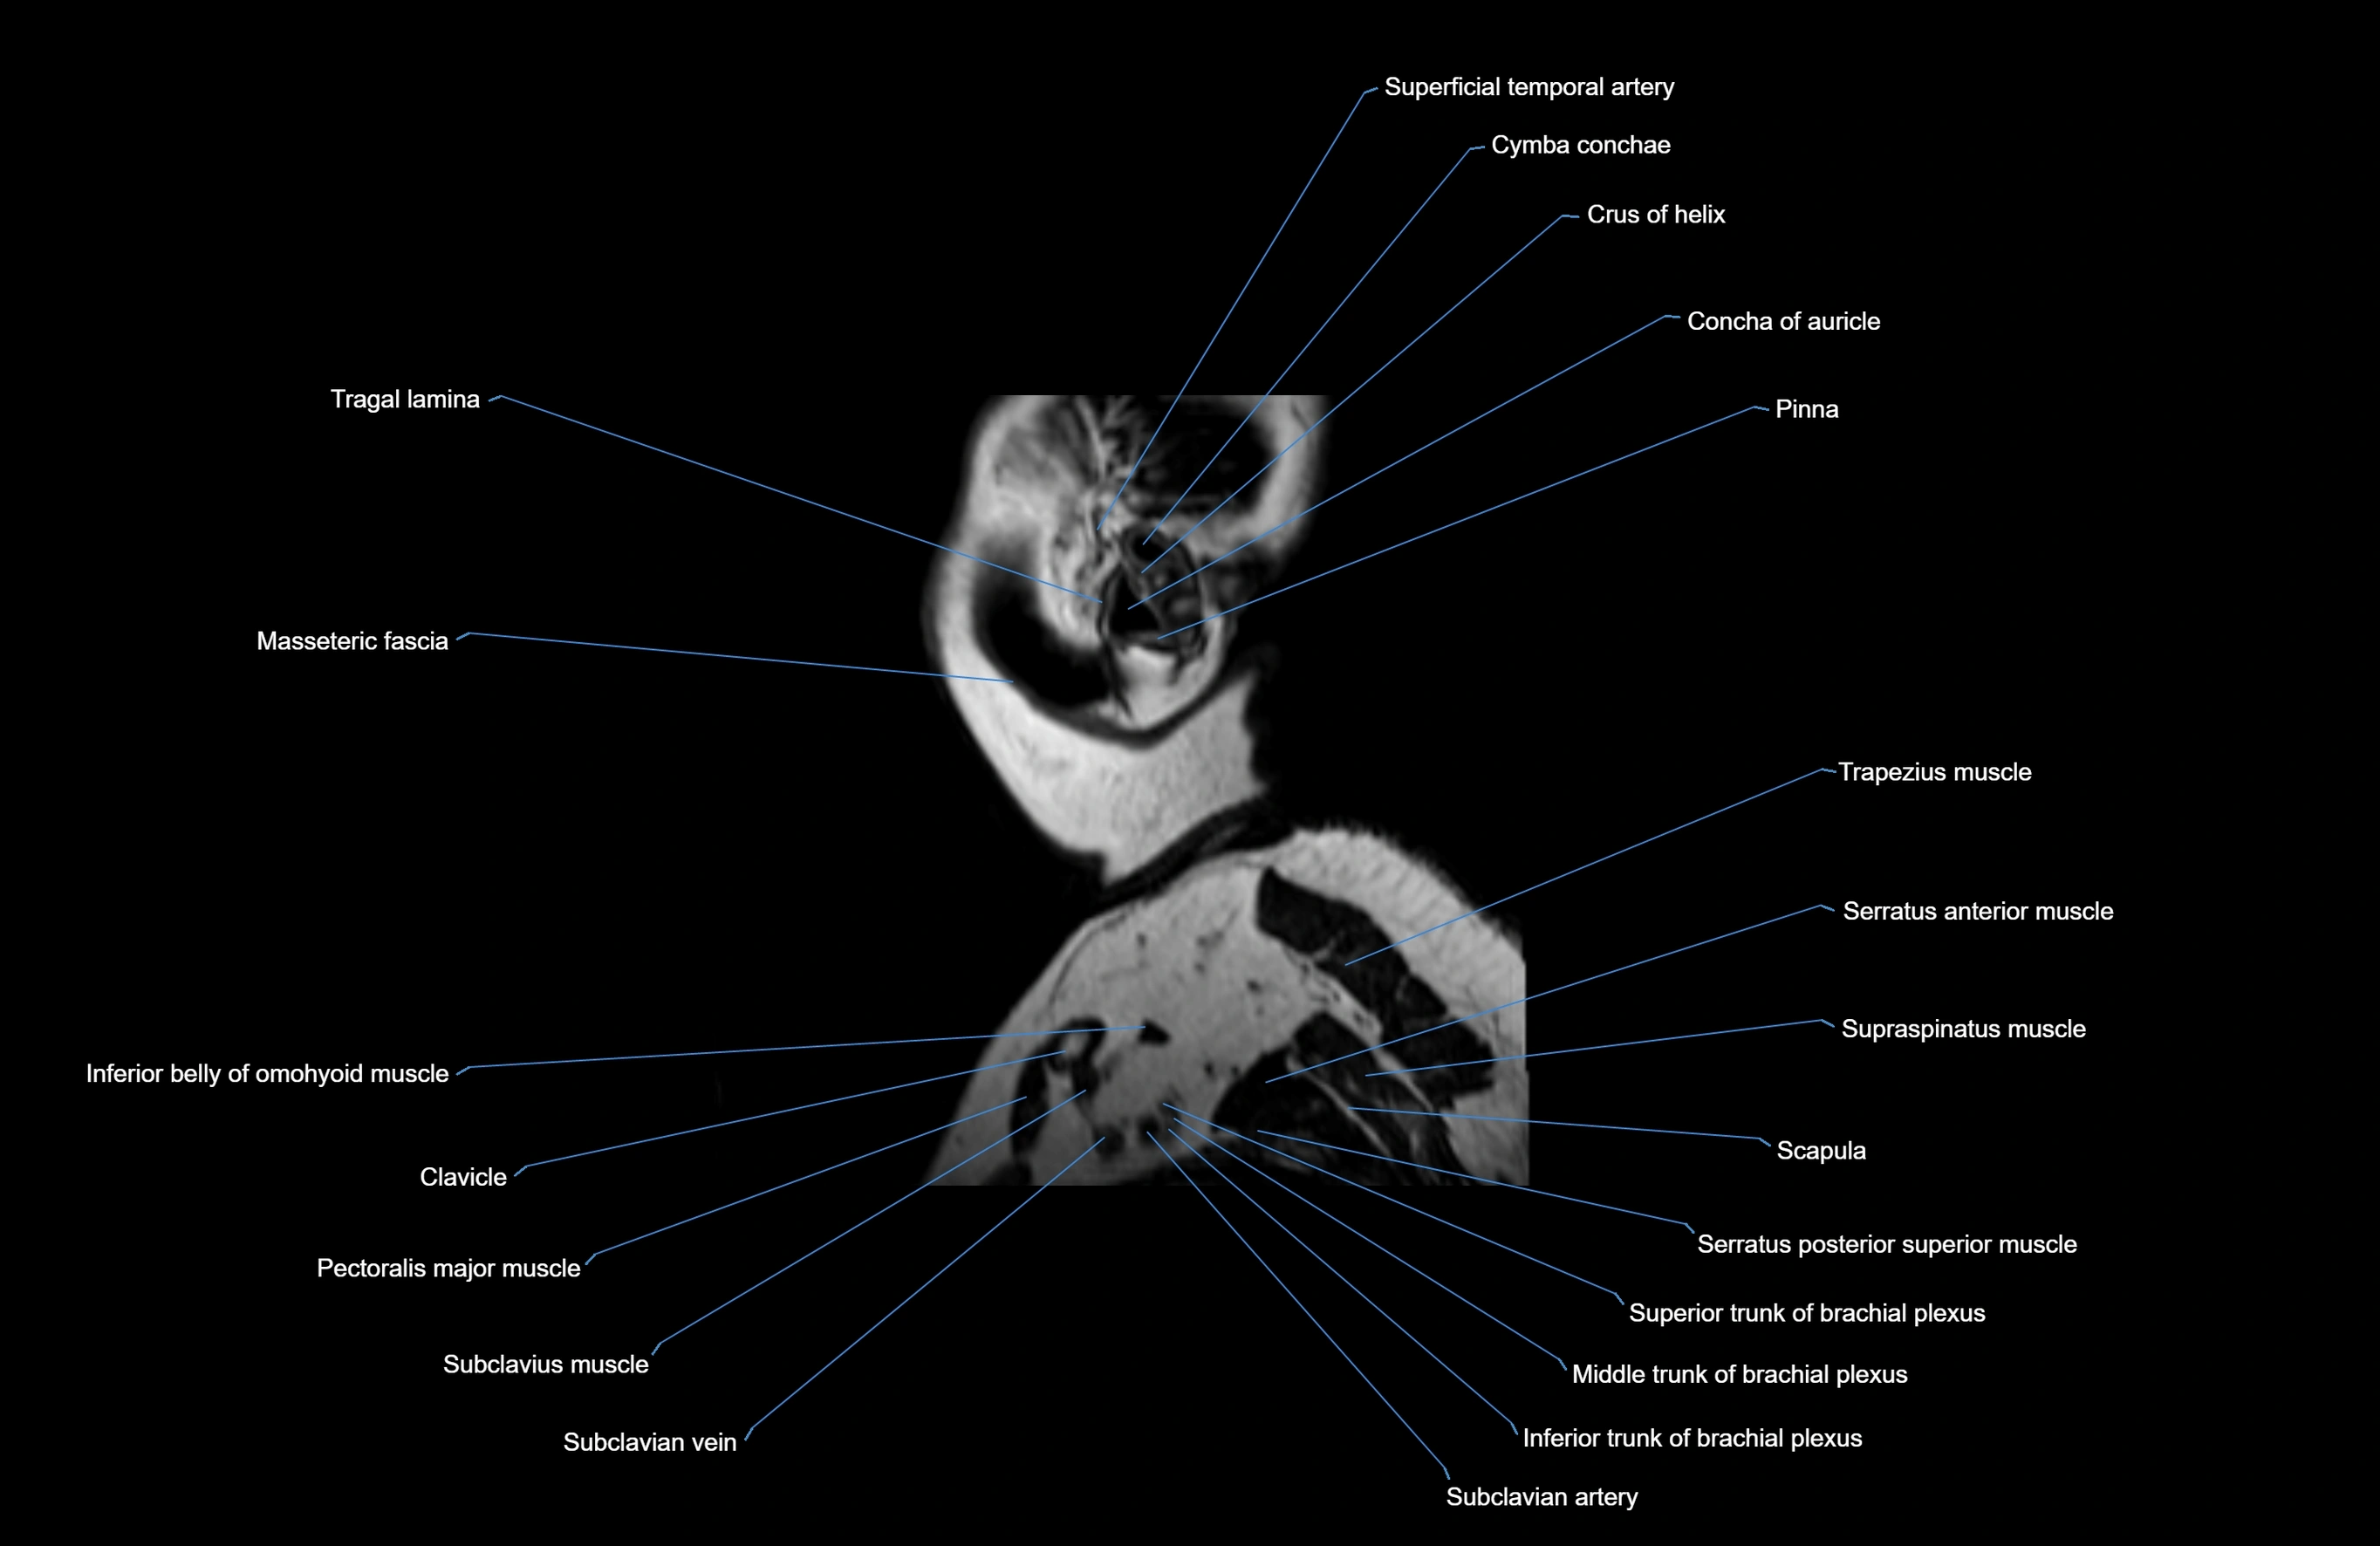

MRI images